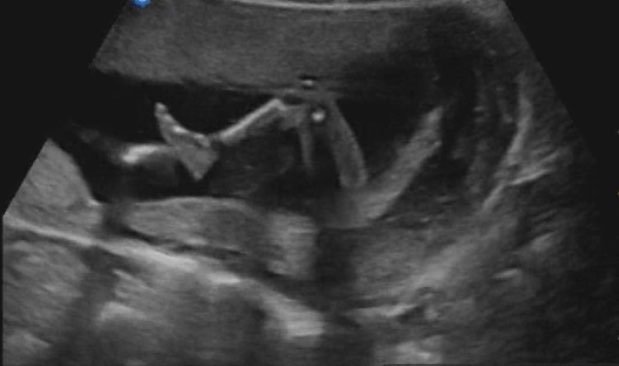

어느 정도 상태를 파악하신 후 조금씩 초음파의 속도를 늦춰가며 입을 떼신다. 염려가 많았던 양수의 양은 계속 적당한 수준으로 매우 좋다고 하신다. 물 먹기의 승리다. 이어 머리의 길이를 재며 뼈 모양을 확인시켜 주시고, 다리의 뼈와 길이도 체크하시면서 예쁨이가 주수에 맞게 건강하게 자라고 있다고 말씀하신다. 키와 몸무게도 알려주시며 다 좋다고 말씀하신다. 아내와 내 삶에서 가장 기쁨이 되고 안도가 되는 반가운 소리이다. 이제 예쁨이는 모든 장기들이 생겨나 발달하고 있고 갈비와 팔다리 등에 뼈도 잘 생겨났다. 초음파를 보면 마치 엑스레이처럼 뼈가 하얗게 보인다. 이 작은 아이의 몸에 모든 게 있다.

허벅지는 아빠를 닮아 벌써 튼튼해 보이고 하체가 발 끝까지 아름답게 쭉쭉 뻗은 것은 엄마를 닮았다. 점과 같은 모습으로 심장만 반짝이던 예쁨이가 어느새 이렇게 진짜 사람의 모습으로 컸다니.. 예쁨이가 진짜 사람이 맞지만 진짜 사람처럼 성장하는 게 신기하기만 하다.

아내의 배에 손을 대고 초음파 영상을 돌려본다. 진짜 예쁨이가 눈 앞에 있고 내 손에 있는데 핸드폰으로 예쁨이의 모습을 만나고 있으니 뭔가 이상하다. 초음파 영상을 자세히 보니 예쁨이가 다리를 접었다가 펴기도 하고 손을 죔죔 하며 오므렸다가 펴기도 한다. 예쁨이의 작은 움직임 하나에도 우리는 흥분한다. 예쁨이가 우리 가정에 찾아와 준 그때부터 지금까지, 그리고 앞으로도 예쁨이의 존재는 우리를 더 행복하게 하고 감사하게 할 것이다. 그날 밤 우리는 서로 감사한 것 세 가지씩 말하기를 통해 빛으로 그늘을 거둬내고 더 좋을 내일로 향했다.